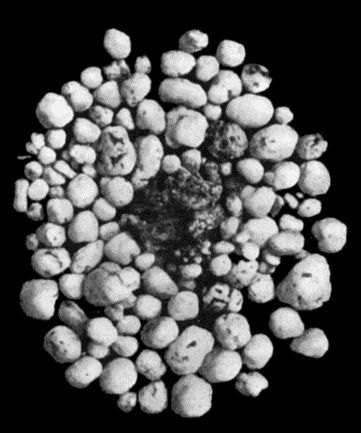

| 30. | Colony of Actinomyces | 126 |

| 168. | Multiple partially ossified Chondromas of Synovial Membrane from Shoulder-joint | 542 |

| 169. | Multiple Cartilaginous Loose Bodies from Knee-joint | 543 |